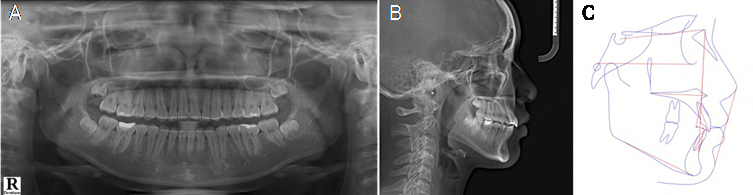

The pretreatment panoramic radiograph showed that all third molars were still developing, dental fillings were present on some molars, and no signs of abnormalities were found in the apical bone base or periodontal tissues (Figure 2.A). A web-based cephalometric analysis software (WebCeph) was employed to produce cephalometric tracing and measurements. Figure 2.B and Figure 2.C present lateral cephalometric X-ray and tracing of the patient prior to orthodontic treatment. The analysis revealed a class III skeletal relation- ship (ANB, 0.220; Wits appraisal, -4.58 mm) and a normodivergent facial pattern (FMA, 25.530). The upper incisors had normal inclination (U1 to maxillary plane angle, 110.690), while the lower incisors were retroclined (IMPA, 83.220). The upper and lower lip were slightly retruded (Upper lip to E-plane, -1.18 mm; Lower lip to E-plane,-1.7 mm) (Table 1).

Figure 2 Panoramic radiograph(A), lateral cephalometric radiograph (B), and tracing (C) before orthodontic treatment.